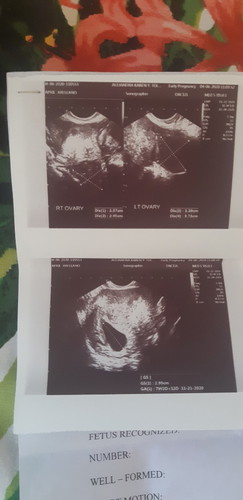

blithed ovum ?

share ko lng mga mommies 2nd ultrasound ko(7 wks).wala pa dng nkitang baby? sbi ng dr.bka blithed ovum kya pinatigil na duphaston ko.ang sakit sakit kc tagal nmin ipinag dasal.after 11 yrs.ito na po yun.ayaw kong mawalan ng pag asa d bali ng late xa makita sana.alam kong ang DIYOS prin ang nkaka alam ng lahat ???? pls.pray for me..ingat po tayong lahat.